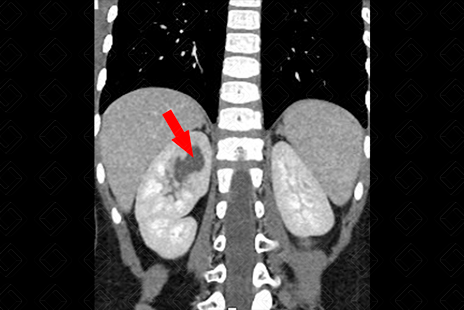

Texto alternativo para a imagem Figura 3. Créditos: Dra. Elazir Mota - Rio de Janeiro/RJ

Descrição da figura 3: Ao avaliar a tomografia do mesmo paciente, observamos a presença de linfonodos calcificados no mesentério (seta vermelha), levando à suspeita de tuberculose como etiologia para necrose capilar, confirmada posteriormente.

• Urotomografia: A pesar da radiação ionizante, tem sido um exame cada vez mais utilizado para confirmar este diagnóstico. Observaremos um cálice convexo com extravasamento de contraste para a papila renal, na maioria dos casos (f iguras 1 e 2) . No caso apresentado, tratava-se de paciente com tuberculose - observe os linfonodos calcificados no mesentério (f igura 3) .